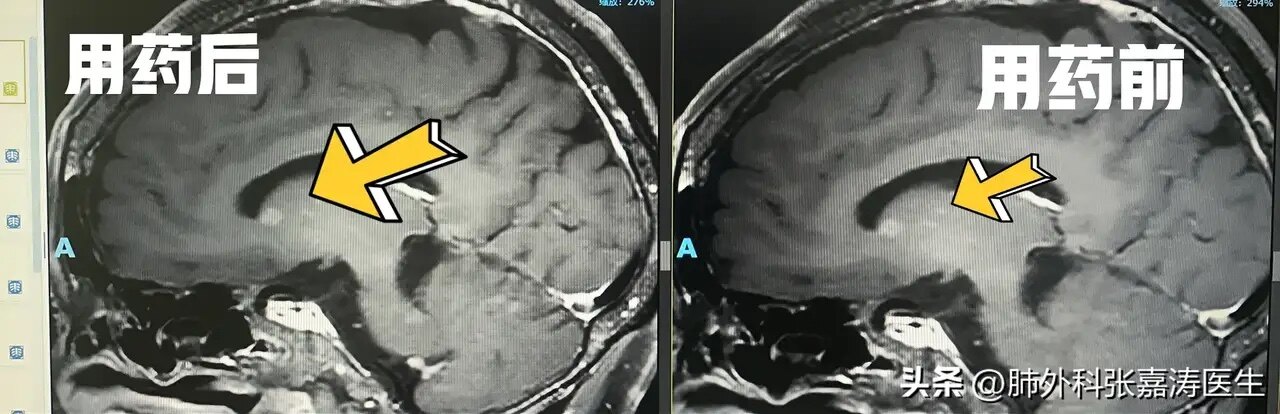

腦轉移瘤(轉移癌)指原發(fā)于身體其他部位的腫瘤細胞轉移至顱內,從而導致腫瘤在顱內生長的一種疾病。最常見的是肺癌腦轉移、乳腺癌腦轉移、胃腸道腺癌腦轉移及甲狀腺癌腦轉移等。臨床表現(xiàn)主要有頭痛、嘔吐、視物模糊、偏癱、語言不清等。患者往往有其他部位腫瘤病史。檢查:頭顱磁共振平掃+增強:顯示最清楚,轉移癌的特點是:小病灶,大水腫。就是較小的腫瘤,瘤周出現(xiàn)大面積腦水腫。頭顱CT平掃主要用于急性發(fā)病時,不能顯示小的轉移瘤。正電子發(fā)射計算機斷層掃描(PET-CT):PET-CT能夠評價腫瘤和正常組織的代謝差異,有助于腫瘤的定性診斷,主要用于尋找全身其他病灶。治療:本著早發(fā)現(xiàn)、早治療的原則,根據腫瘤大小、位置、數目、病人身體狀況、有無高顱壓等綜合判斷,決定最佳處理方案,如手術、放療、化療或靶向治療等。1、手術治療:由于血腦屏障的存在,腦轉移瘤化療效果有限,放療在有明顯高顱壓時禁忌,而且放療后可出現(xiàn)認知功能下降等后遺癥的存在,因此單個占位效應明顯的腦轉移瘤可以考慮手術治療。a.腦內單發(fā)、部位適合、易于切除,且腫瘤或其水腫占位效應重或導致腦積水的患者適合外科手術切除。原發(fā)灶隱匿或雖原發(fā)灶明確但取材困難的可行定向活檢明確病理。b.多發(fā)腦轉移瘤外科手術治療目前尚有爭議,但一般認為:若腫瘤數目≤3個,且手術能完全切除,則應盡早手術。>3個腦轉移病灶的治療應首選全腦放療(WBRT)或立體定向放療(SRT)但如果出現(xiàn)腫瘤出血壞死、梗阻性腦積水等危及生命的癥狀和特征時,也應行手術減壓,為下一步放療或內科治療爭取時間和空間。c.腫瘤大?。耗[瘤最大徑>3cm者,一般不適合放射治療,宜首選手術;腫瘤最大徑<5mm,尤其位于腦深部(丘腦、腦干等)宜首選放療;如腫瘤最大徑為1~3cm,則根據患者全身狀況、手術風險等綜合評估,再決定首選手術還是其他治療。d.腫瘤部位:盡管目前借助神經導航、術中功能定位等技術,神經外科醫(yī)師的技術可以到達顱內任何一個部位,但腦深部或功能區(qū)轉移瘤手術的致殘率總體上較淺表或非功能區(qū)的手術致殘率高。因此,對位于腦干、丘腦、基底節(jié)的腦轉移瘤,原則上不首選外科手術,首選放療。e.轉移癌導致腦積水:轉移瘤引起腦脊液循環(huán)障礙,出現(xiàn)腦積水,會導致患者頭痛頭暈、惡心嘔吐,病情可迅速惡化,昏迷,腦疝死亡。此時急診手術,才可能為后續(xù)綜合治療贏得時機。如果是某個轉移腫瘤引起腦室梗阻,可以考慮直接切除該腫瘤,如果是腦膜轉移,或者無法直接切除腫瘤解決腦積水,可以行腦室腹腔分流術,將梗阻的腦脊液通過皮下隧道管腔引流到腹腔(腹膜吸收腦脊液)救命。2、放療(1)全腦放療:彌漫性轉移灶、廣泛腦膜轉移的患者;(2)立體定向放療:對于僅有單個轉移灶或轉移灶數量小于4個的患者、顱內轉移灶切除術后的輔助治療3、藥物治療、化學藥物治療及靶向治療根據原發(fā)腫瘤類型不同,結合病理和免疫組化結果,可適當選擇化療藥物或靶向藥物治療,具體藥物應咨詢相應??漆t(yī)生(比如呼吸科、消化科、乳腺外科等)、腫瘤化療科醫(yī)師,神經外科醫(yī)生一般不太熟悉具體化療藥物附典型案例:1.單發(fā)大于3cm的轉移癌:患者女性,肺癌術后14年、腦轉移癌術后6年余(2010年4月肺癌手術確診,2017年發(fā)現(xiàn)單個腦轉移瘤,經夏成雨醫(yī)生主刀手術切除,繼續(xù)腫瘤放療科和腫瘤內科化療綜合治療)2.小腦孤立性轉移癌引起梗阻性腦積水,合并肺部腫塊典型案例:患者男性,46歲,頭痛頭暈1周加重伴惡心嘔吐急診入院。頭顱ct、磁共振平掃+增強顯示:左側小腦半球腫瘤伴水腫,腦積水,肺部ct顯示左下肺5厘米左右腫塊。入院時患者頭痛明顯,必須甘露醇暫時緩解高顱壓,否則隨時發(fā)生死亡,此時唯一有效的措施是切除小腦腫瘤解除腦室梗阻,否則患者很快顱高壓加重腦疝發(fā)生死亡,手術順利切除腫瘤,腦積水緩解,術后病理證實肺癌腦轉移,該患者順利康復出院,接著靶向藥物治療。3.多發(fā)性轉移癌,其中一個轉移癌占位效應明顯典型案例:患者,男性,56歲,右肺癌伴顱內多發(fā)轉移,已不適合肺癌切除手術,其中右顳葉轉移癌腫瘤最大直徑3.75cm左右,腫瘤周圍大面積腦水腫,導致腦中線結構移位,出現(xiàn)高顱壓(頭暈頭痛)。此時放療,腫瘤不一定會縮小,并且腦水腫必然加重,患者很有可能度不過放療后腦水腫加重關發(fā)生腦疝死亡,因此手術切除最大的那個腫瘤,可獲得標本做基因檢測分析,看有無靶向藥。術后水腫逐漸消退,標本做基因檢測分析有靶向藥,肺部腫塊服藥后體積也顯著縮小過程中??梢娫摶颊呤中g獲益明顯,為后續(xù)治療爭取了機會。4.腦膜轉移,腦積水